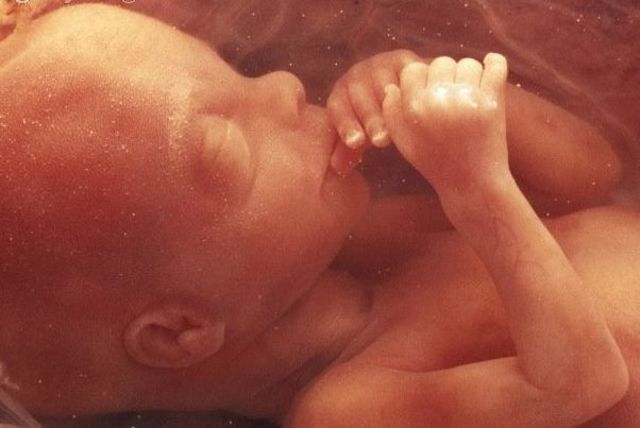

• AUNMENTO DE PESO

AUNMENTO DE PESO

El bebé está comenzando un período en el que aumentará rápidamente de peso y longitud. Ahora tiene aproximadamente entre 6.5 y 7.5 cm de largo y pesa entre 14 y 21 gramos.Durante esta semana de embarazo las orejas y los ojos se están moviendo hacia su posición. Ya han aparecido los 27 huesos de la mano y pronto el bebé comenzará a chuparse el dedo.